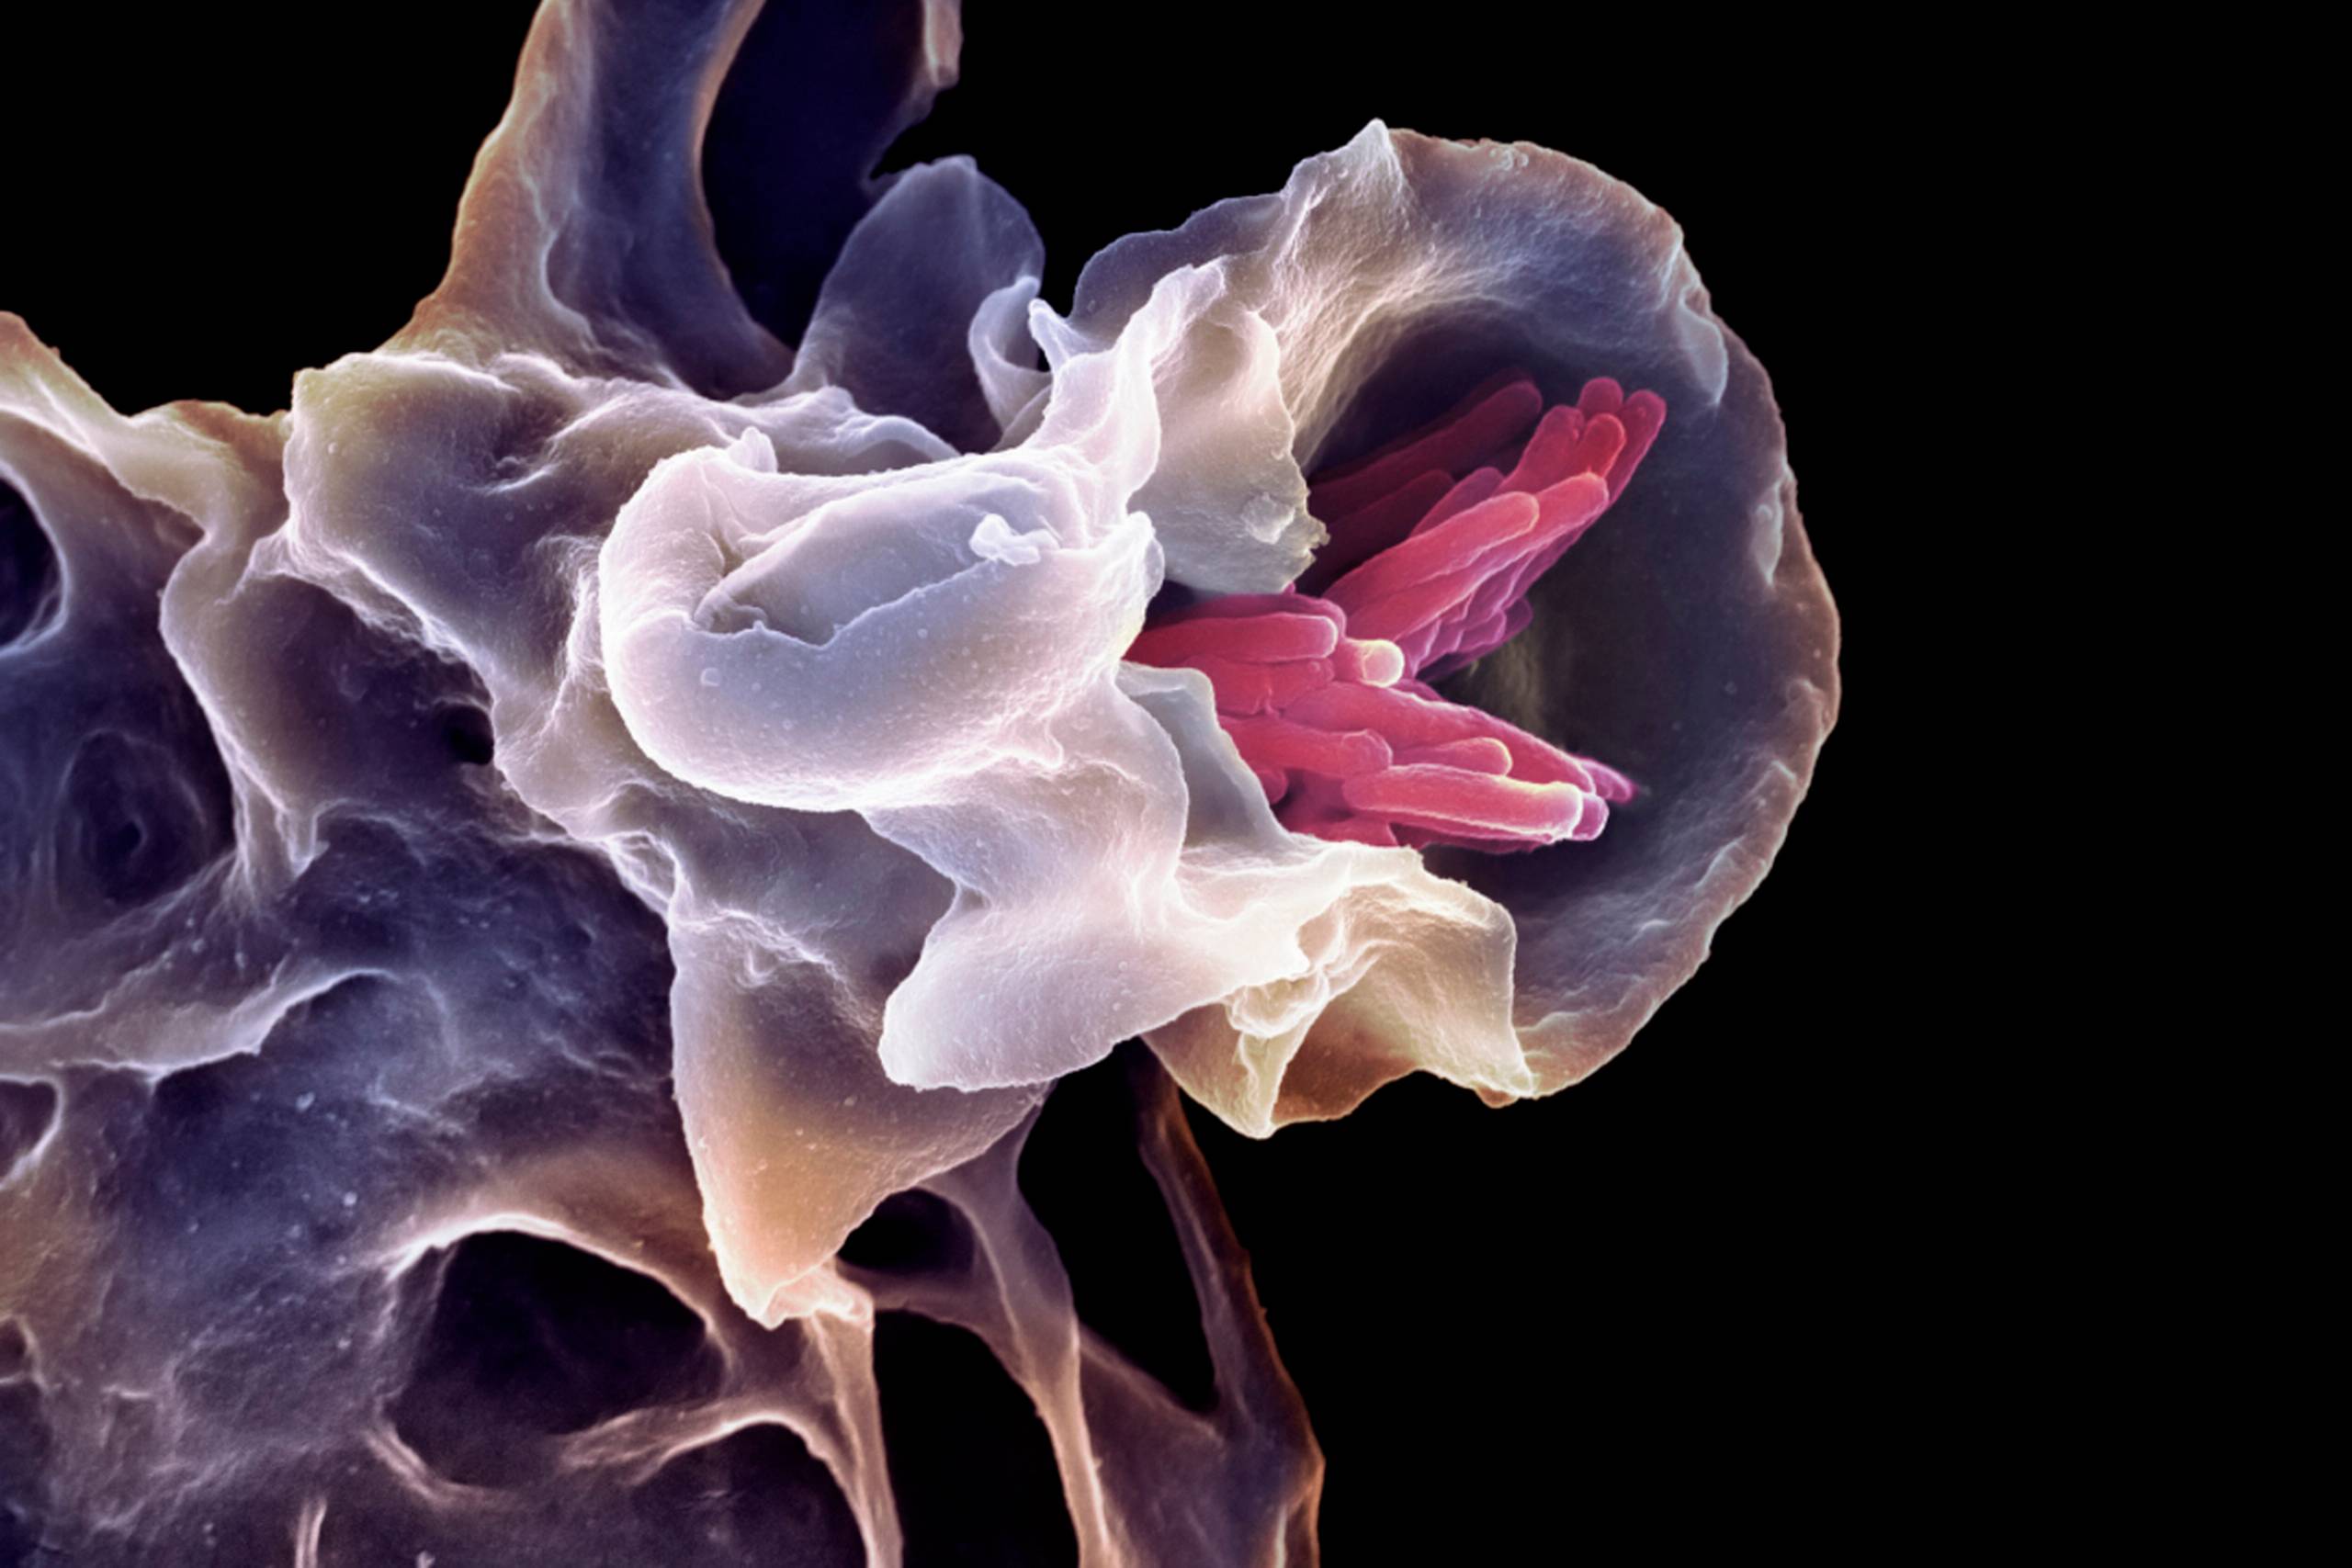

24. Bakterier – et mikroskopisk liv